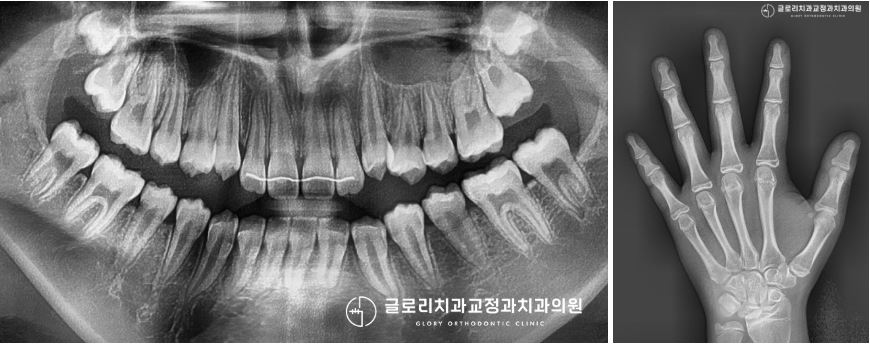

다행히 성장판 검사를 진행해 보니

완전히 늦진 않은 것으로 확인이 되었습니다.

늦은 감이 있다는 것을 보호자께 설명드렸는데요.

얘기를 듣고 나신 후 어떻게든 수술을 피하고 싶다며

치료에 대한 강한 의지를 보여주셨는데요.

중랑구교정치과 에서는! 어머님의 굳은 의지를 보고

상악골 확장을 동반한

페이스 마스크를 진행하기로 했습니다.